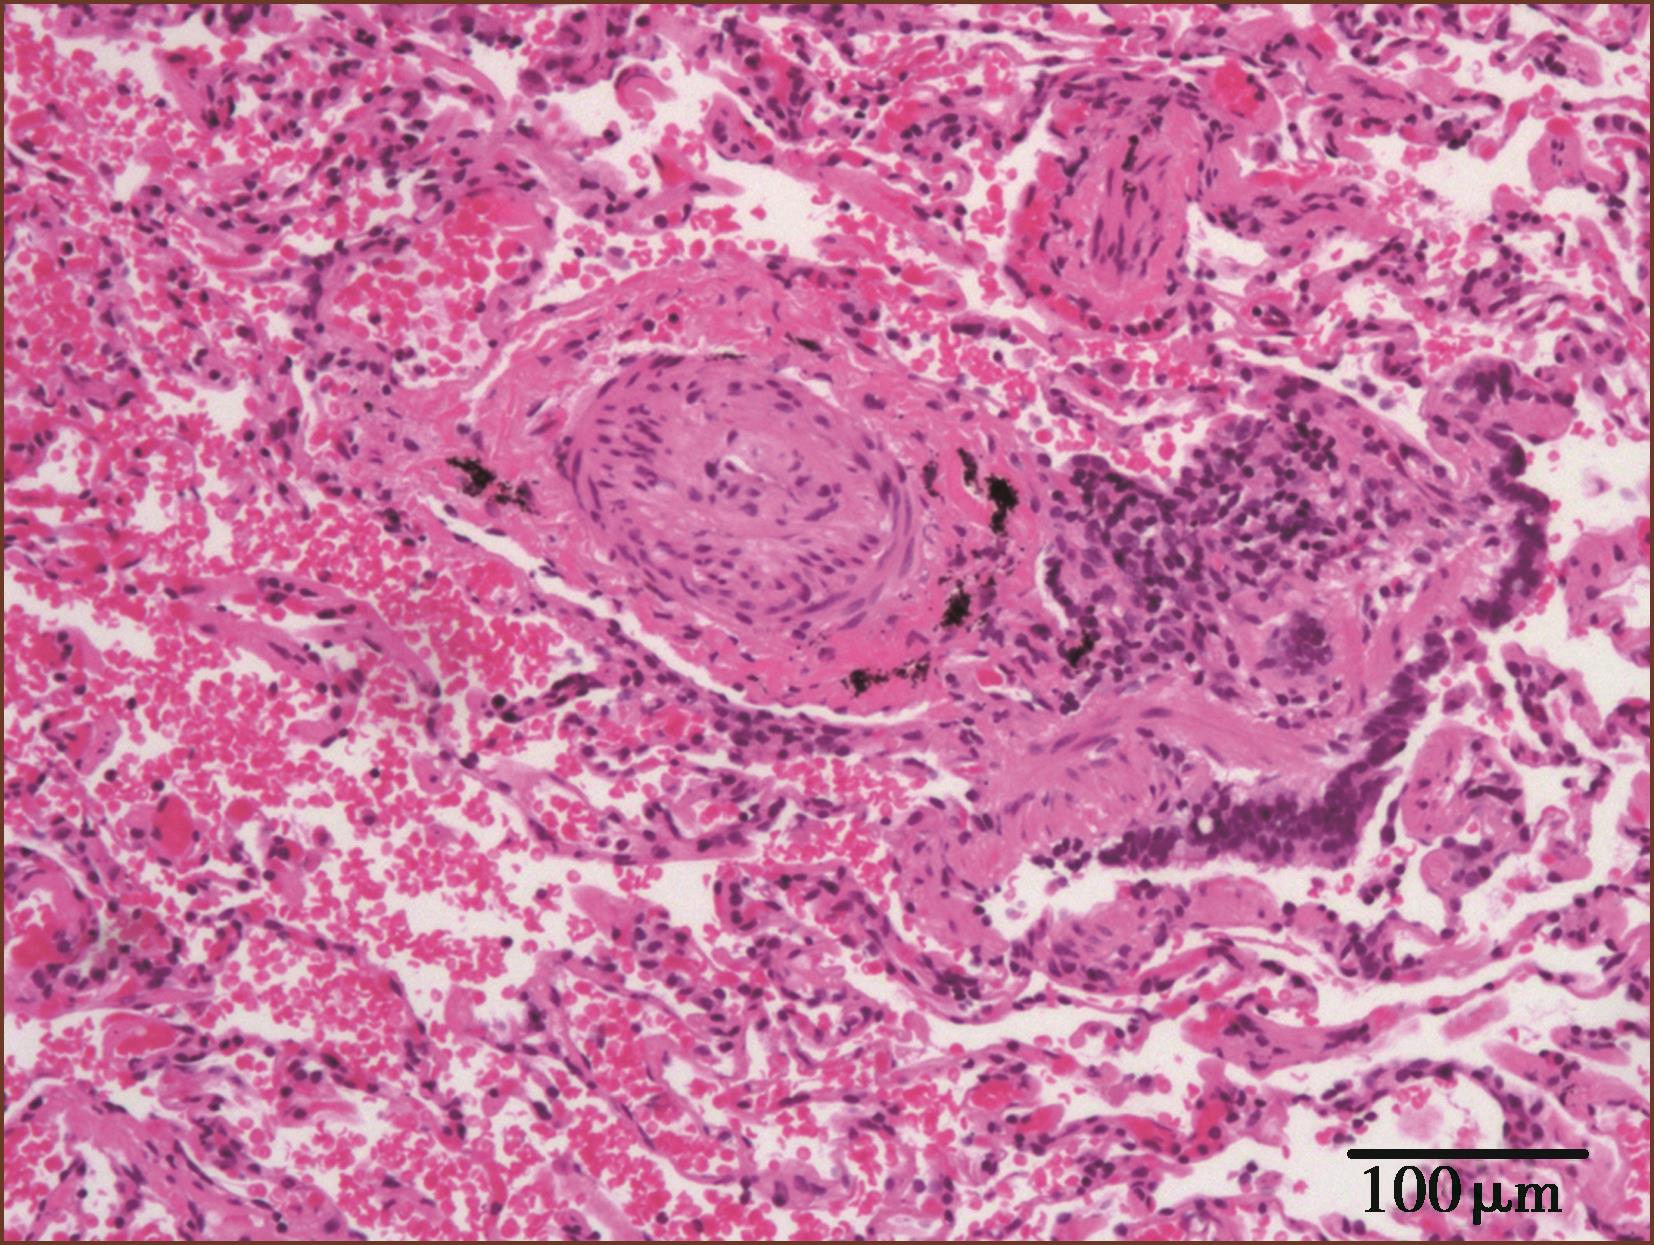

引起肺动脉栓塞主要的原因是下肢深静脉血栓脱落,不同口径的肺动脉栓塞产生的结果也不同。外周肺小动脉栓塞常常没有症状,只在尸检时偶然发现。反复发生的肺小动脉栓塞会引起肺动脉高压。大的肺动脉血栓栓塞会引起右心功能衰竭、低血压和循环衰竭而猝死。病理学上,急性肺动脉血栓栓塞,肉眼及显微镜下可见左、右肺动脉及肺内小动脉内充满暗红色血栓物质(图3-2-1, 图 3-2-2)。

慢性栓塞时,肺动脉内膜增厚,多为机化血栓(图3-2-3)。血栓可以再通,在原有机化血栓基础上又可见新鲜血栓形成(图3-2-4,图3-1-8)。

图3-2-4 肺动脉内新鲜及机化血栓(HE,低倍放大)

肺动脉血栓形成及/或栓塞病引起肺毛细血管床破坏、肺细小动脉中层肥厚、内膜纤维化狭窄或闭塞。

没有可靠的标准区别是原位血栓形成,还是栓塞,一般认为,大肺动脉的血栓阻塞可能来自栓塞,常为急性;肺动脉末梢分支血栓阻塞可能是原位的血栓形成。肌型肺动脉血栓很可能是原发的,虽然肺小动脉广泛的微栓也可从大块血栓崩解而来。慢性血栓性肺动脉病常常伴发肺动脉高压,血栓的病理变化特征是不规则的、非板层状闭塞性内膜纤维化,有机化再通的血管,有时为血管内纤维性单一分隔或网状分隔。可伴有肺毛细血管芽增生,像丛状。血栓后病变的可逆性是很有限的。有的病人临床有不能解释的肺动脉高压,其肺肌型动脉有多个新旧血栓阻塞;但其体静脉无栓塞病史,此种被称为安静型反复发生的血栓栓塞性肺动脉高压(silent recurrent thromboembolism pulmonary hypertension),又可称为慢性血栓栓塞性肺动脉高压(CTEPH)。此种微栓可能由于原发的血栓形成,而不是栓塞。我们也遇到过此种原因不明的特发性肺动脉高压,临床误诊为先天性心脏病或间质性肺病。在血栓后的肺小动脉纤维斑块内可见含铁血黄素沉着或钙化。在有些血栓阻塞型肺动脉高压病例,肺小动脉中层肥厚不如动脉性肺动脉高压那样的明显,而以内膜纤维化及血栓改变明显。